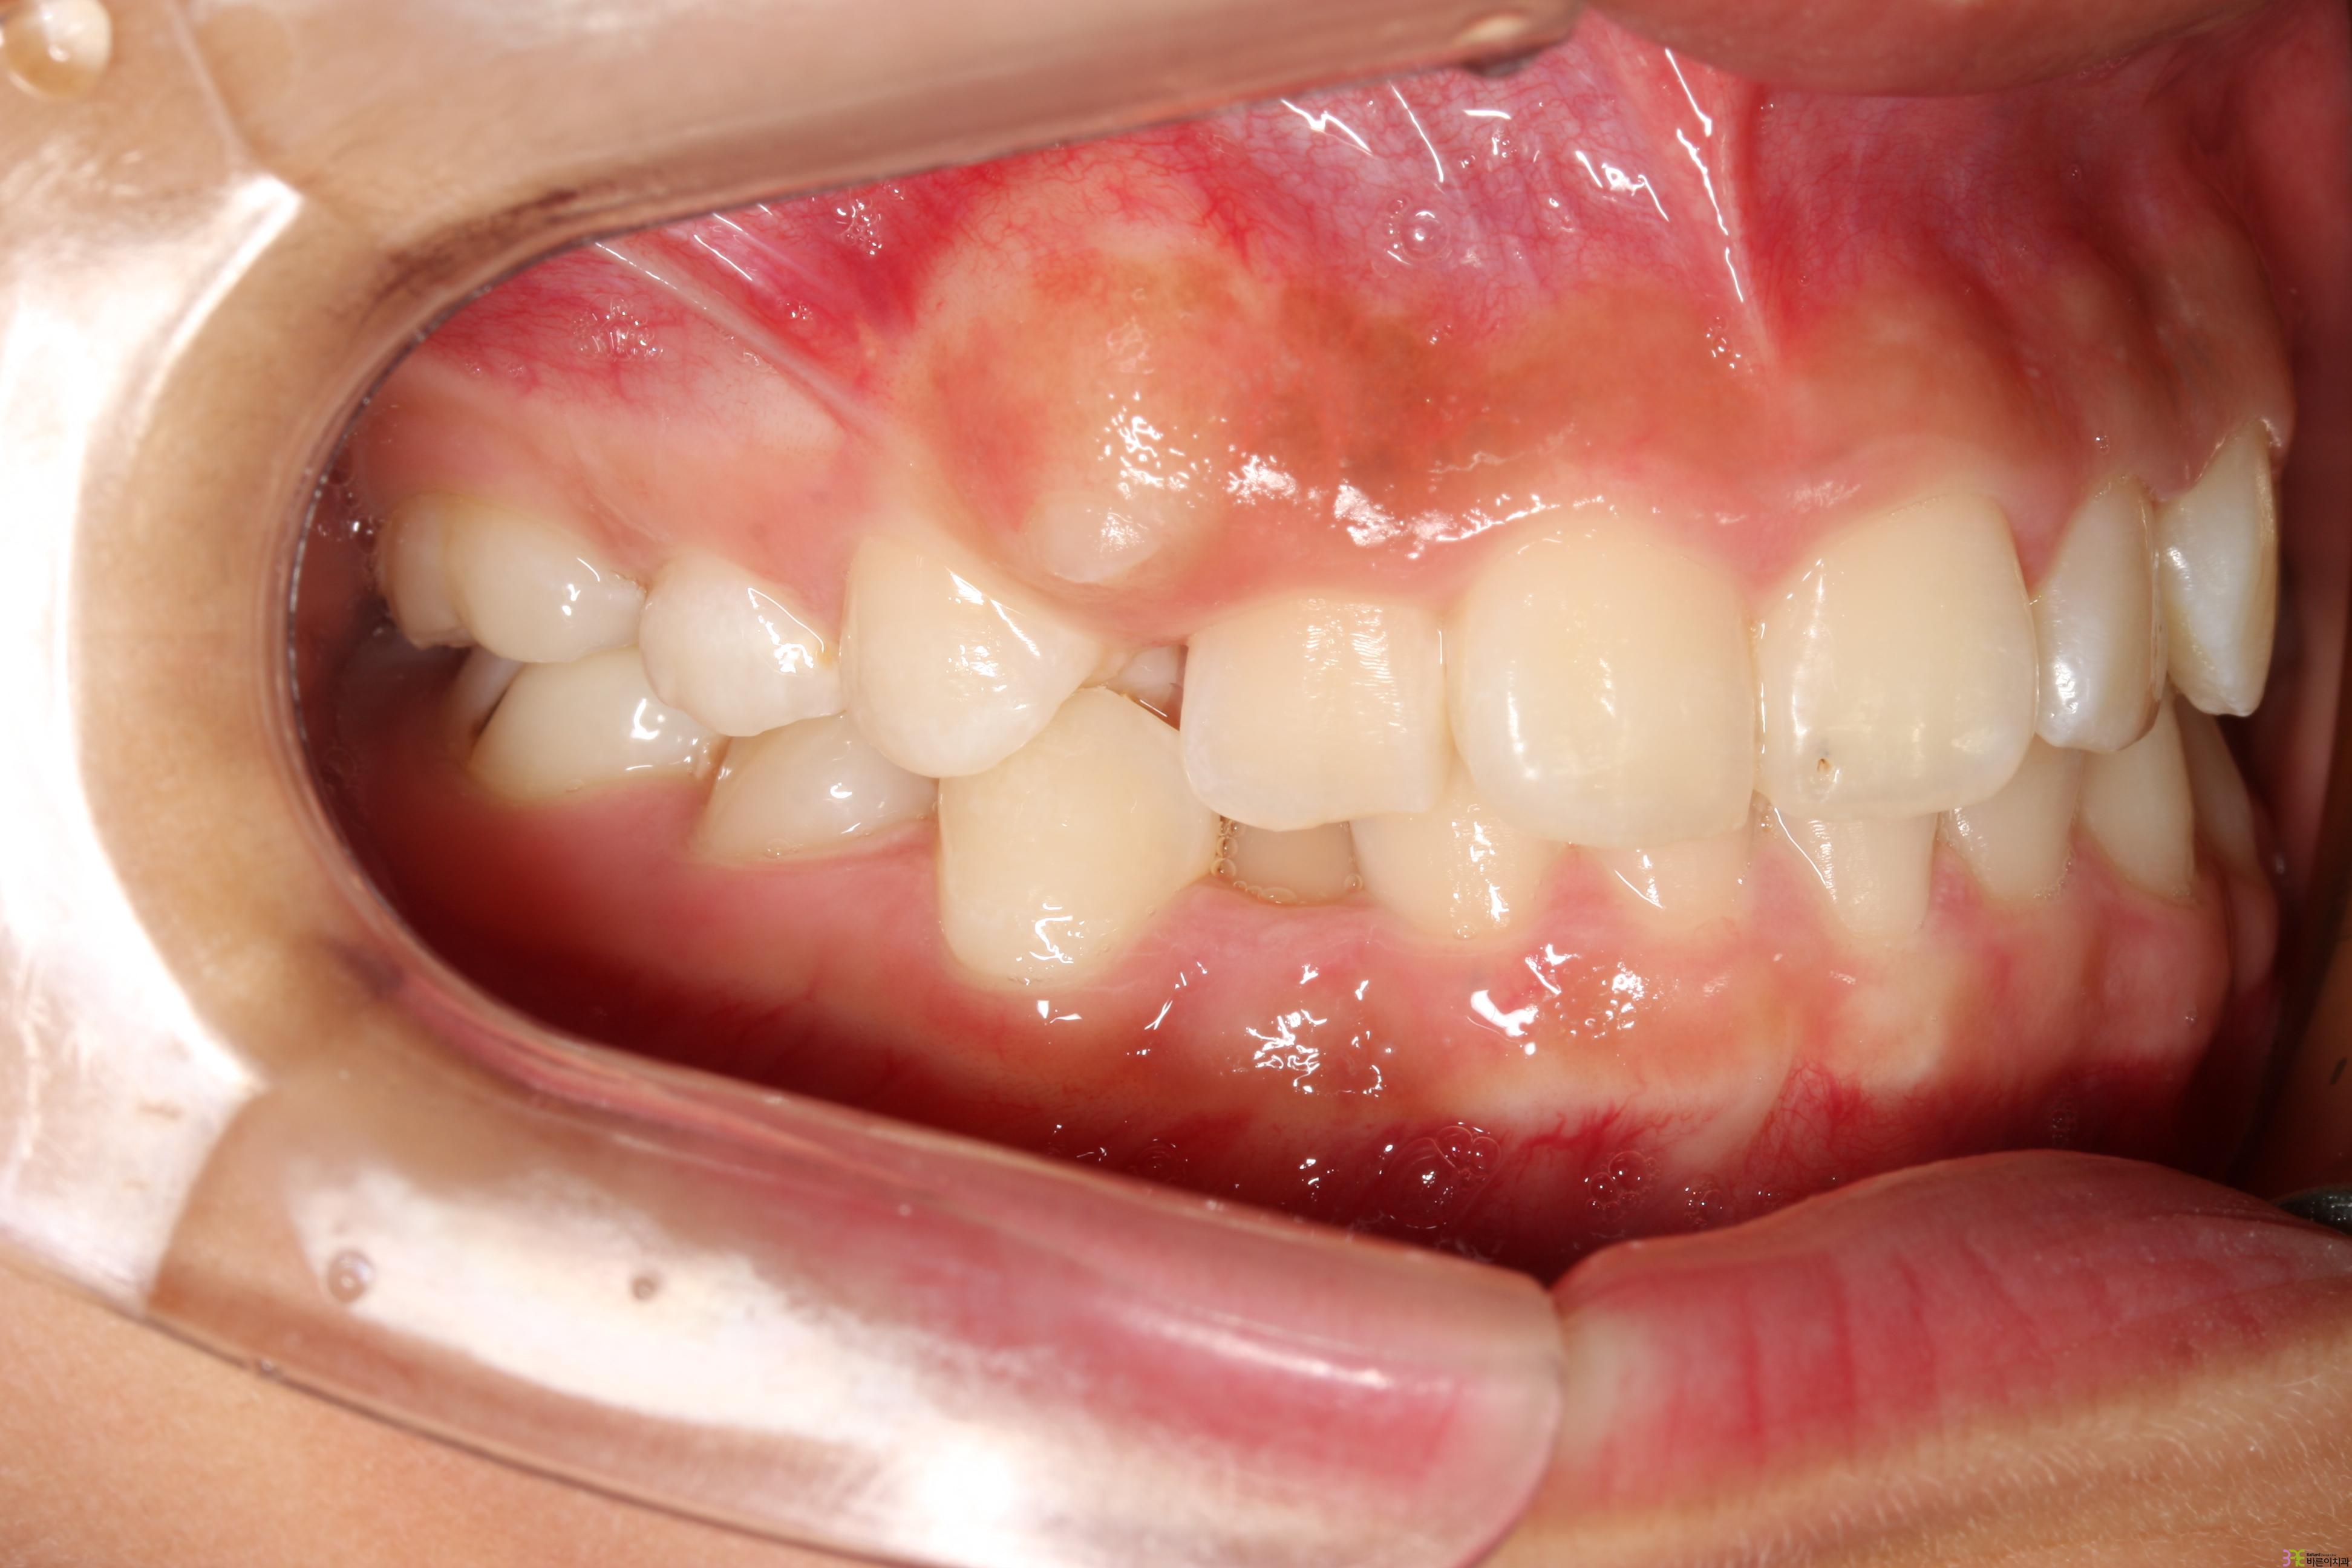

치료명

덧니교정

치료기간

1년

Before

After